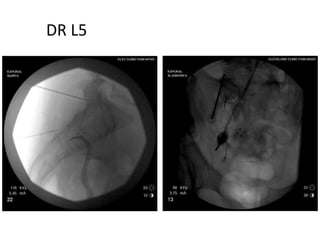

Technique 2. L5 PrimaryDorsal Ramus Lesioning

Tips & Tricks Firstdo the dorsal ramus L5 RF lesioning in the awake patient (as for a facet joint denervation) Then start IV sedation

• 56.

A solution containinglidocaine +/‐ steroid solution is injected through the RF cannula, and radiofrequency lesioning of the L5 dorsal ramus is performed at 85 °C for up to 90 seconds

• 58.

Probe is 2mmoff bone for distal lesion projection